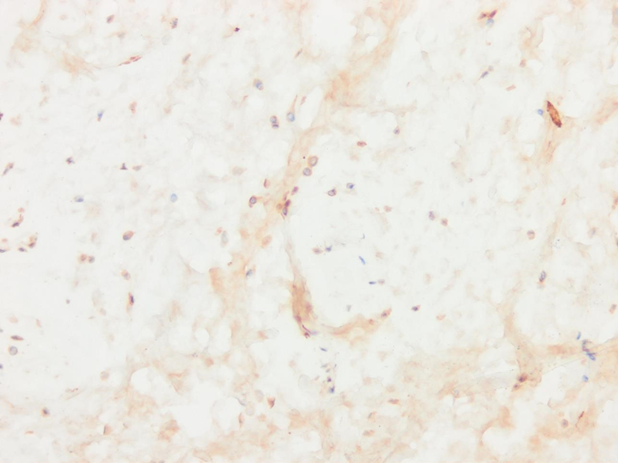

Immunofluorescent LHR stain in ruptured CCr : Score 6/6 based on Kiefel and Kutzler 2020

HPG hormone screen of patient in CCr study

LHR study of the stifle in CCr patient included in the study